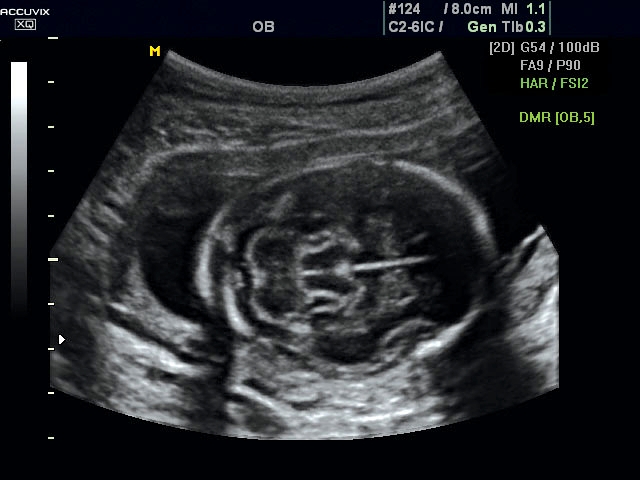

A pontos analízis és diagnózis iránti egyre növekvő igény kiszolgálására a MEDISON egy új real time képfeldolgozó technológiát fejlesztett ki Dynamic MR™ elnevezéssel. Az eljárás a diagnosztikus ismeretanyagot a precizitás és a pontosság egy teljesen új szintjére emeli. Használata az alapvető 2D ultrahang képinformáció real time, kivételesen kristálytiszta és kiemelkedően részletezett megjelenítését teszi lehetővé tűéles kontúrok és finoman rajzolt szövetstruktúra mellett. A DMR™ technológia ideális eszköze az ultrahang-diagnosztikának kezdve a szülészet-nőgyógyászattól a foetalis echon át az általános alkalmazásokig.

A DynamicMR alkalmazása az átlagos ultrahang teljesítményt a zaj és szemcsézettség jellegű műtermékek kiszűrése révén a vizuális diagnosztika, a precizitás és a pontosság új szférájába emeli. Figyelje meg a cerebellum, CSP és cisterna magna élstruktúráit, mennyire pontosan definiáltak és a teljes agyi struktúra ábrázolása a Dynamic MR alkalmazásával milyen látványosan javul.